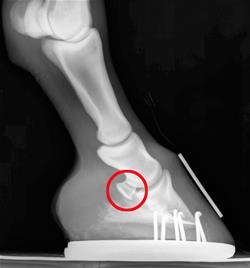

Burba will discuss navicular syndrome, what it is, how it is diagnosed, and if certain horses are predisposed to this problem. He will also talk about treatment and management considerations for this problem.